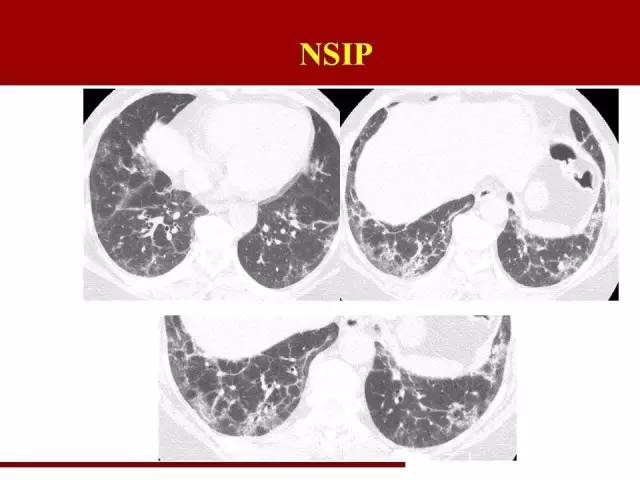

NSIP诊断条件相对放松一些

分布和UIP一致,不同的是磨玻璃阴影多于网格状阴影,可以伴有牵拉性支气管扩张

那么在这里提到两个概念

间质性肺炎的磨玻璃阴影:病理基础为小叶内间质增厚,即肺泡表面的间质发生炎症,覆盖部分肺泡,使肺泡密度增高,形成磨玻璃阴影。在NSIP中,这部分磨玻璃阴影代表着可逆部分,也就是说及时治疗有可能能恢复肺泡功能。因此影像科在报告的时候尽量能把磨玻璃阴影提出来,以便临床进行疾病严重程度评估。

这是NSIP

磨玻璃影比较明显,有可能可以可逆,这部分肺组织的保护很重要

影像科对间质性肺炎的分类的意义大致在此吧